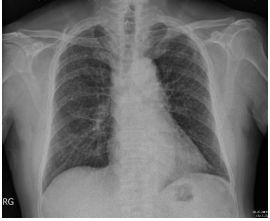

1. A 39-year-old man had this chest X-ray on his health exam. No any clinical symptoms.